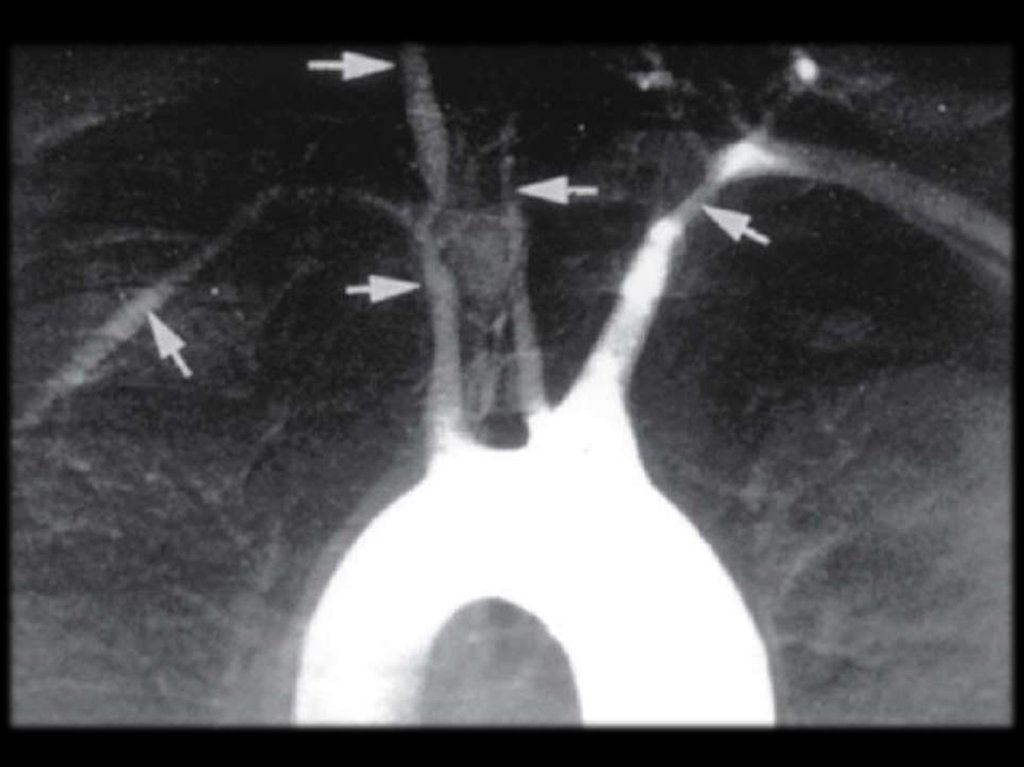

Узелковый полиартериит – ангиограмма сосудов кишечника

Узелковый полиартериит – ангиограмма сосудов почек